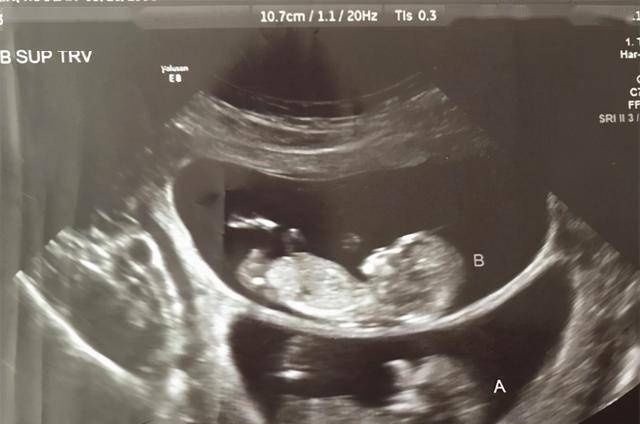

偏差|孕妇做B超时,医生总是说胎儿比实际天数多几天是为什么?

所以,孕妈们在产检的时候,最怕出现的就是有不一样的检查结果发生,有的孕妈在做B超的时候,总是会冷不丁地听到医生对着B超结果说上一句:XX偏大一周。于是,孕妈听完之后就会变得很紧张,偏大一周是怎么回事?是宝宝有什么问题吗?其实,孕妇做B超时这种情况是经常发生的,而医生总说胎儿的检查结果显示要比实际天数多几天是为什么?

一、B超测量是一个估算测量很多人都会误以为仪器检查出来的结果就是最为准确的, 但是事实上很多仪器的检查结果都会存在一定的测量偏差,而且也都是在实际使用过程中也是允许这样的误差偏差出现的,因为这些情况是无法被完全抹除的。 相对于直接测量的结果, B超产检这种通过超声波的方式,隔着妈妈的肚皮、子宫和羊水的多重障碍来测量宝宝的发育情况,其中存在的误差就更多了。所以,在临床的检查上,B超只能算是一个接近实际的估算测量,并不等于宝宝的实际发育情况。

而且,B超对于胎儿发育情况的估算,主要参考的几个数值是: 双顶径、头围、腹围、股骨长、头臀径等 的各个肢体长度。然后再通过这些测量出来的数值来做发育情况的对比,从而间接的得出宝宝具体的发育情况,这就比较容易在对比之中存在着发育早晚的情况。 导致这种测量比实际情况多几天的原因主要有:1、胎儿 个体发育的差异: 医生的测量参考都是一个相对平均的标准数据, 但实际上胎儿个体的发育是有快慢的差异的。有的宝宝发育得比较早,有的宝宝发育得比较慢,这样就很容易检查结果与实际孕周发育有偏差的情况发生。

2、母体营养供给情况差异:每一位妈妈身体的营养吸收与供给的情况也是不一样的,有 的妈妈营养比较好,那么胎儿的吸收好,自然也就长得比较好;有的妈妈饮食营养摄取量不多,胎儿吸收不够好,发育也就会落后一些。 3、胎儿骨骼发育差异:在B超的测量中,数据的大小基本来源于胎儿身体骨骼发展, 有些时候胎儿的头部骨骼发育比较大,而身体的骨骼发育比较短,这样对比之下也会出现偏大的情况发生。而这些也都不会影响到胎儿的正常发育。

二、B超遇到这种情况需要警惕很多时候,医生口中说得“多几天”都是不影响妈妈们的孕周判断的,而医生也没有表达出特别的态度,妈妈们就不用为此而感到担忧。 最值得妈妈们注意的一点就是,B超与实际天数相差两周以上的情况。因为B超的误差是有一定的正常范围的, 在排除了测量错误之外,那么就只能说明胎儿存在发育早熟的问题,可能有早产的风险。孕妈们需要按照医生的嘱咐进行及时的调整,以免在后期胎儿发育中出现危险性的问题。

重要提示:B超检查属于各个间接的估算结果,因此与实际情况会存在一定的偏差,胎儿的个体发育情况,母体营养供给以及胎儿骨骼发展差异等都会影响检查的结果。而妈妈们更需要警惕的是那种,误差水平之外的巨大偏差。